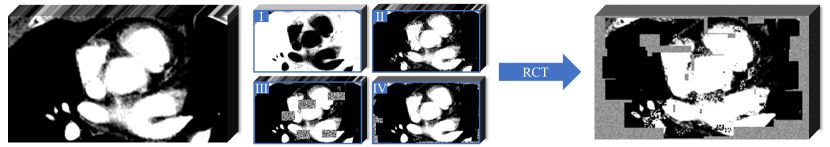

Refer to caption

Figure 2: The transformations used to generate the input for self-supervised training: I. Non-linear transformation, II. Local pixel shuffling, III. In-painting, IV. Out-painting. RCT (Randomly Composed Transformation) means that the basic transformations are composed, each with a probability to be used. Note that in-painting and out-painting are not performed together each time.

An appropriate pretext task can empower neural networks to learn low-level and high-level features that are conducive to downstream tasks (Jing and Tian, 2020). Zhou et al. (2021) introduced a self-supervised method called Model Genesis, which performs an image reconstruction process, and has shown promising results for downstream supervised segmentation tasks. Therefore, we use Model Genesis to pre-train the dual-branch network. Unlike the original Model Genesis that only trains one decoder, we extend it by training two decoders for the reconstruction process during pre-training.

Model Genesis (Zhou et al., 2021) employed three types of transformations on the original images, as detailed in Fig. 2: 1) Non-linear transformation integrates the Bézier Curve (Mortenson, 1999) to assign a unique determined value to each pixel, encouraging the model to focus on the information of image appearance and intensity distribution. 2) Local pixel shuffling samples a window smaller than the model’s receptive field in the patch and rearranges the internal pixels to encourage the model to learn the local texture and boundary. 3) Out-painting or In-painting: Out-painting sets the outer pixels of a shape to random values, while the inner pixels retain their original intensities. In-painting follows the opposite way. The network learns visual features of images by reconstructing the original images from the corrupted version. In the self-supervised pre-training as shown in Fig. 1(a), the outputs from the main and auxiliary decoders compute the Mean Squared Error (MSE) MSEsubscript𝑀𝑆𝐸\mathcal{L}_{MSE} separately with the original image y𝑦y. The reconstruction loss is defined as: